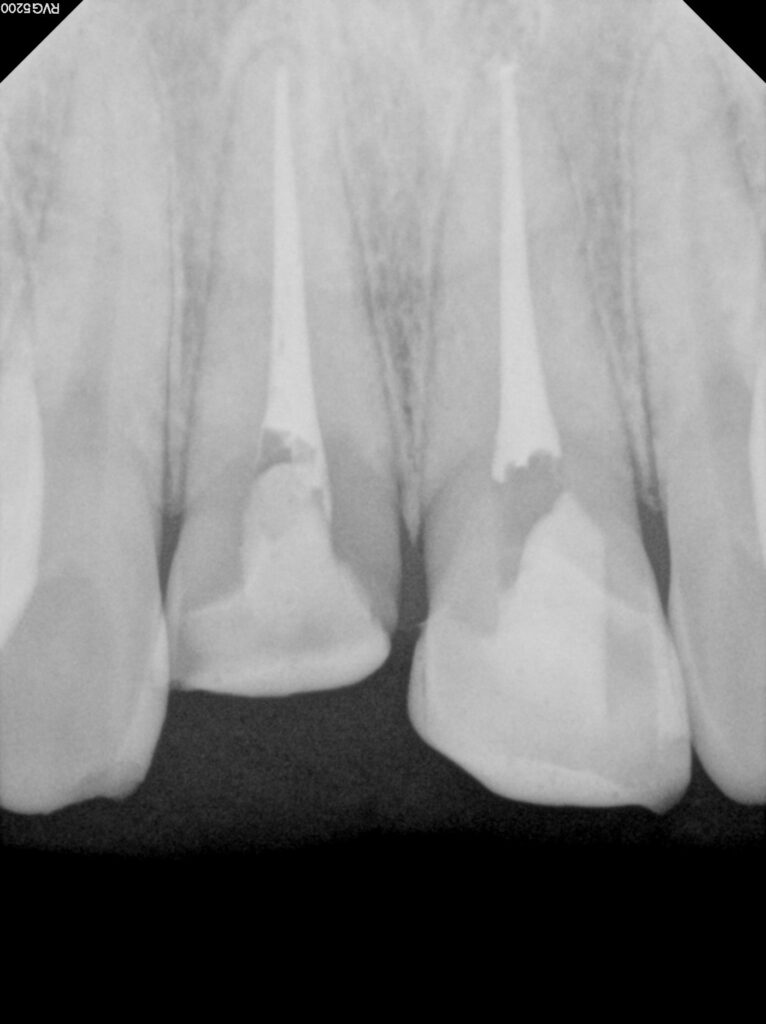

예시 사진을 보면

앞니의 2/3이상이 부러져 사라진 것을

확인할 수 있는데요.

2025.02.12

그로 인해 11번의 경우

자연치 내부 치수가 드러난 것을

볼 수 있으며,

21번은

치수가 드러나지 않았지만

많은 양의 치질이 사라져 있습니다.

바로 신경치료 인데요.

당일에 바로 진료를 진행하여

통증과 감염 가능성을 줄이는 것이

중요합니다.